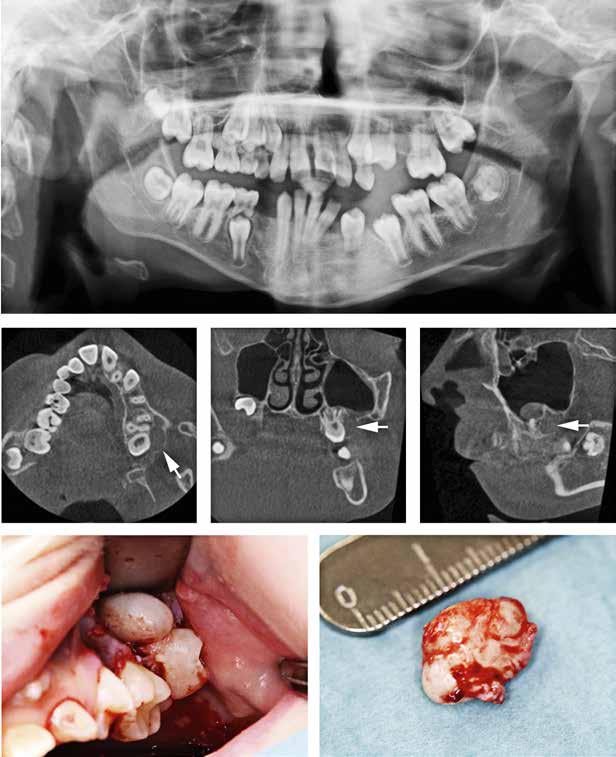

Udbyttet af disse nordiske fællesmøder kan vise sig i så konkrete tilfælde som et patienttilfælde med en udiagnosticeret otteårig pige, født med mitralklapinsufficiens, lav legemshøjde (-2 SD) og dysplastiske tænder med frembrudsproblemer og spontane nekroser til følge. Casen fremlægges på et møde, hvor to af deltagerne mener at have set lignende (Fig. 1A, B). Efter endt møde fremsendes yderligere information fra Aarhus med opfordring til, at der kunne være en mutation i LTBP3-genet, også

Panoramarøntgen 4 og 7 år

Fig. 1. A. 4-årig pige ved henvisning. Primære incisiver mistet på grund af spontane nekroser. Primære og permanente tænder ses dysplastiske og stort set uden emalje. B. Nu som 7-årig. 6’erne er endnu ikke frembrudt, men ses resorberede under slimhindedække. Der ses pulpaoverkapninger og endodontisk behandling af 1+, som har virket efter hensigten og bevaret tænderne i fronten. Endodontisk behandling på yderligere et antal tænder må forudses.

Fig. 1. A. 4-year-girl at the time of referral. Primary incisors have been lost because of spontaneous necrosis. Both permanent and primary dentition is without enamel and with dysplastic morphology. B. Same girl as 7-year-old. Molars are still not erupted but are seen to be resorbed preerupted. There has been done endodontic treatment in several teeth in the front, which has given function for now. It must be taken into account that more teeth will need endodontic treatment in the future.

kaldt DASS (Dental Anomaly and Short Stature). Efter yderligere henvisning til afdeling for klinisk genetik finder man en sygdomsfremkaldende variant i netop det gen (4). Pigen kan nu gå i relevant kardiologisk opfølgning og på sigt blive tilbudt relevant genetisk rådgivning og eventuelt prænatal diagnostik, når hun en dag selv ønsker at få børn. Ud over dette blev tandbehandlingen også drøftet i det nordiske forum. Patienten har siden tandfrembrud fået foretaget enkelte profylaktiske pulpaoverkapninger

og forseglinger af kronerne for at forebygge spontane nekroser. Dette gøres for at sikre tændernes bevarelse under væksten. På sigt forventes tænderne at mistes og erstattet implantatprotetisk, når dette findes relevant. Samtlige behandlinger er varetaget i højspecialiseret regi, men patienten følges også i primærsektoren, hvor samarbejdet mellem netop hospitalsbehandlingerne og kommunal tandpleje findes af stor betydning.